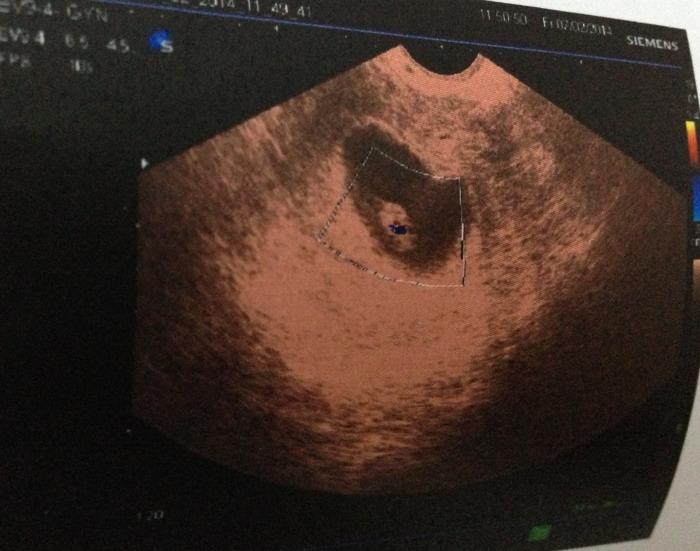

1、胎囊(GS)

胎囊也叫孕囊,胎囊只在怀孕早期见到。月经28~30天规则来潮的妇女,停经35天,B超就可以在宫腔内看到胎囊。

胎囊的位置:胎囊位置在子宫的宫底、前壁、后壁、上部、中部都属正常;形态圆形、椭圆形、清晰为正常;如胎囊为不规则形、模糊,且位置在下部,孕妇同时有腹痛或阴道流血时,可能要流产。

胎囊的大小:怀孕6周时胎囊直径约2厘米,孕10周时约5厘米,孕1.5个月时直径约2厘米,2.5个月时约5厘米为正常。